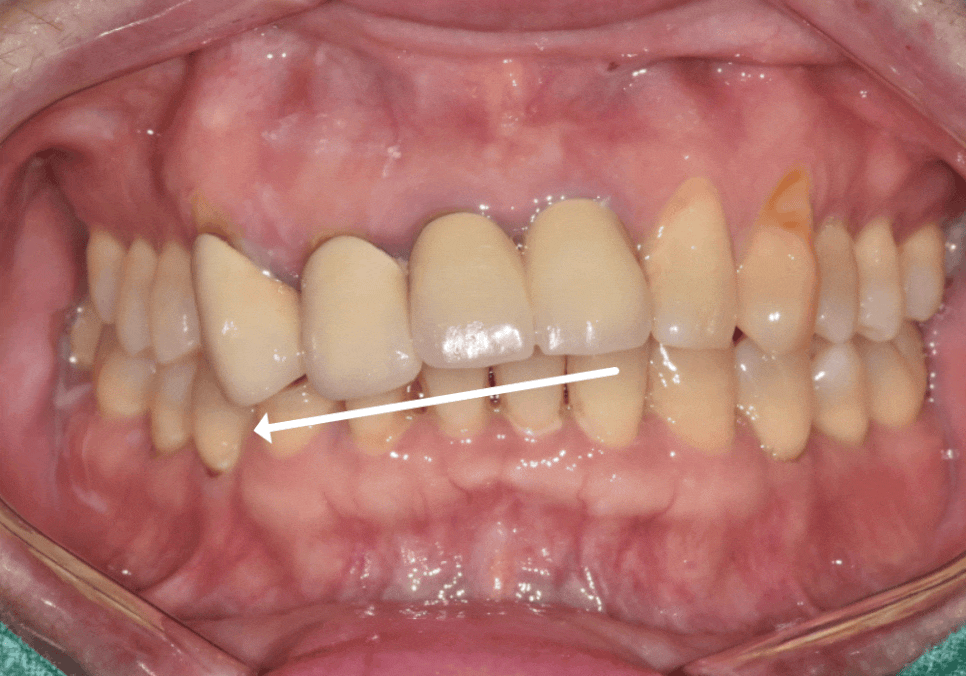

신경 치료를 마친 뒤,

가장 중요하게 생각한 것은

'웃을 때의 앞니 라인'이었습니다.

다만, 고민스러운 지점이 있었습니다.

삐뚤어보였던 치아 라인이

보철 치료를 통해

눈에 띄게 개선되었습니다.

특히 구강스캐너와 원내기공소의

디지털 시스템 덕분에,

더욱 신속하면서도

정교한 보철물을 완성할 수 있었습니다.

230215(전) 230726 (후)

앞니가 삐뚤다고 해서

무조건 교정만이 답은 아닙니다.

치아 상태와 목적에 따라,

보철 치료가 시간과 비용을

아끼는 현명한 대안이 될 수 있습니다.